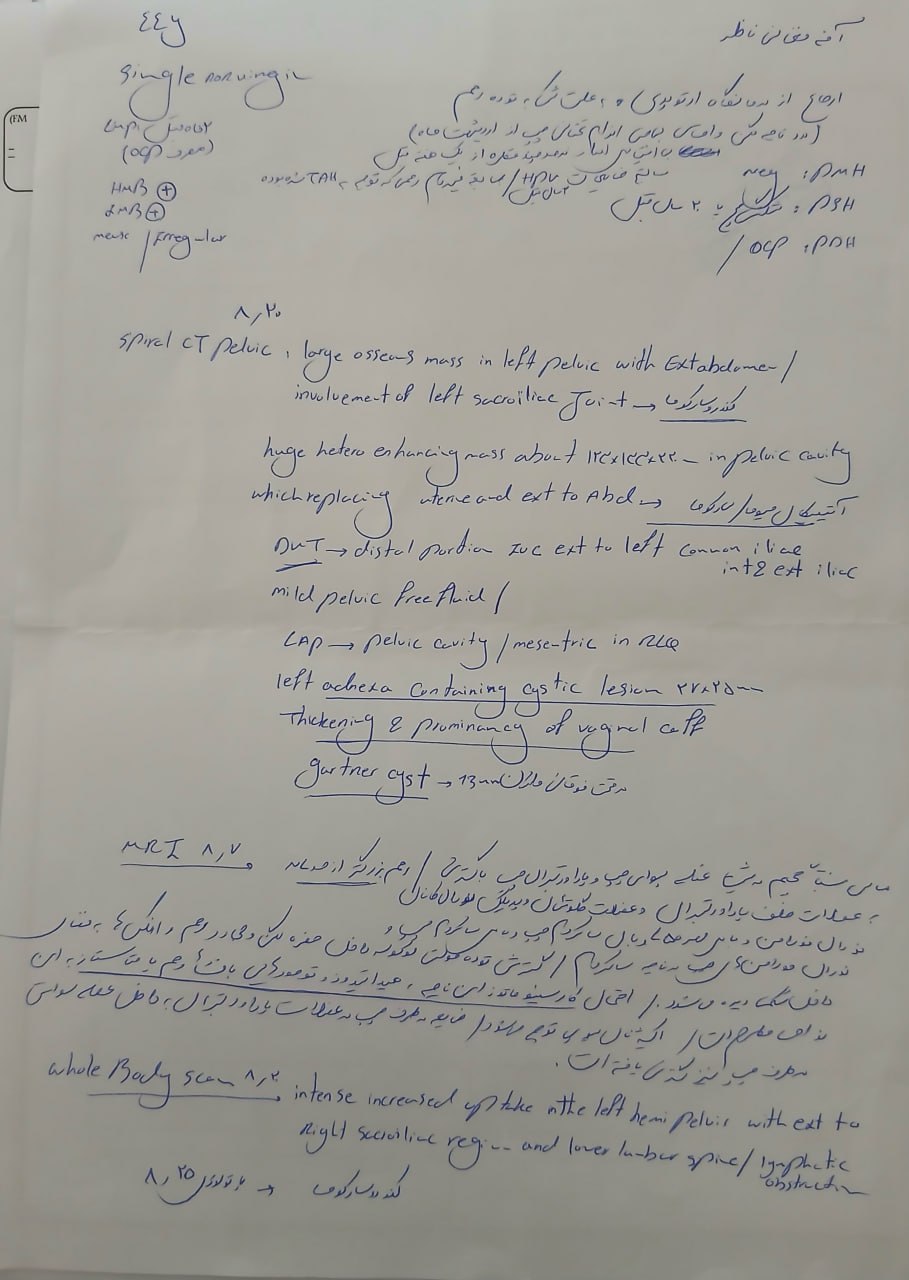

در بررسیهای تصویربرداری (MRI)،در تاریخ 24.7 ، تودهای با تشخیص کندروسارکوما همراه با DVT گزارش شده است. بیمار سابقه درد لگن داشته که شدت آن در حال حاضر نسبت به گذشته کاهش یافته است. به گفته بیمار، حجم توده در ابتدا در حدود اندازه یک تخممرغ بوده که در حال حاضر کاهش یافته است. همچنین تورم اندام تحتانی در حال حاضر نسبت به قبل کمتر شده است.

بیمار، در تاریخ 18.9 ، به دلیل تورم اندام تحتانی چپ از سرح ران و درد شدید سراسر اندام تحتانی چپ به همراه اختلاف سایز اندام ها در تهران بستری شده است. در بررسیها جهت بیمار تشخیص ترومبوز ورید عمقی (DVT) اندام تحتانی چپ مطرح شده است و تحت درمان DVT قرار گرفته است.

مراجعه کرده است. پس از بررسی های انجام شده در MRI انجام شده توده با درگیری مفصل ساکروایلیاک چپ و DVT؛ ابتدا تحت درمان DVT قرار گرفته است و سپس جهت پیگیری تومور رویت شده تحت بیوپسی قرار گرفته است و با تشخیص کندروسارکوما به این مرکز مراجعه کرده است و تحت کموتراپی و رادیوتراپی قرار گرفته و سایز تومور کاهش یافته است.